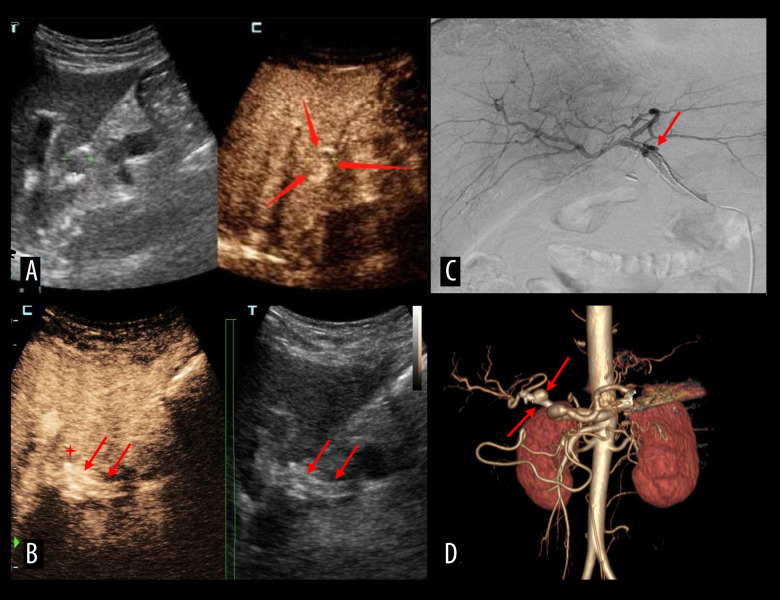

肝动脉血栓形成是肝移植术后最常见、最严重的血管并发症。经导管动脉溶栓具有高选择性、低剂量、局部药物浓度高、对全身凝血功能影响小等优点。动脉内对比增强超声(IA-CEUS)无辐射,可重复,可在床边进行,可作为连续监测的替代方法。我们描述了IA-CEUS在评估连续经导管动脉溶栓治疗肝移植后肝动脉血栓形成的效果中的有效性。材料与方法选取2016年11月至2023年5月肝移植术后诊断为肝动脉血栓形成的患者8例。所有8例患者均采用尿激酶连续经导管动脉溶栓。在溶栓治疗期间,对每位患者进行IA-CEUS动态监测。采用肝动脉数字减影血管造影对结果进行验证。结果2例患者出现肝动脉灌注缺损。6例患者动脉灌注良好。3例患者出现胆囊瘤。一名患者患上了夹层动脉瘤。一名患者出现假性动脉瘤,导管移位。1例患者出现腹膜后血肿。所有患者均未出现造影剂相关并发症。结论IA-CEUS作为评价经导管动脉溶栓治疗肝移植术后肝动脉血栓疗效的新选择是安全可行的。

BACKGROUND Hepatic artery thrombosis is the most common and severe vascular complication after liver transplantations. Transcatheter arterial thrombolysis is a viable alternative with high selectivity, low drug dosage, high local drug concentration, and minimal effect on systemic coagulation function. Intra-arterial contrast-enhanced ultrasound (IA-CEUS) is radiation-free and repeatable, can be performed bedside, and could be an alternative for continuous monitoring. We described the efficacy of IA-CEUS in assessing the effect of continuous transcatheter arterial thrombolysis in post-liver transplant hepatic artery thrombosis in a series of cases. MATERIAL AND METHODS Eight patients with diagnosis of hepatic artery thrombosis after liver transplantation between November 2016 and May 2023 were selected. All 8 patients underwent continuous transcatheter arterial thrombolysis, using urokinase. Dynamic IA-CEUS monitoring was performed for each patient during the thrombolysis treatment. Hepatic artery digital subtraction angiography was used to verify the results. RESULTS Two patients showed a hepatic artery perfusion defect. Six patients demonstrated good perfusion of artery. Three patients developed biloma. One patient developed a dissection aneurysm. One patient developed a pseudoaneurysm with catheter displacement in it. One patient developed retroperitoneal hematoma. None of the patients experienced contrast agent-related complications. CONCLUSIONS IA-CEUS was found to be safe and feasible as a new option for evaluating the efficacy of transcatheter arterial thrombolysis in post-liver transplant hepatic artery thrombosis.